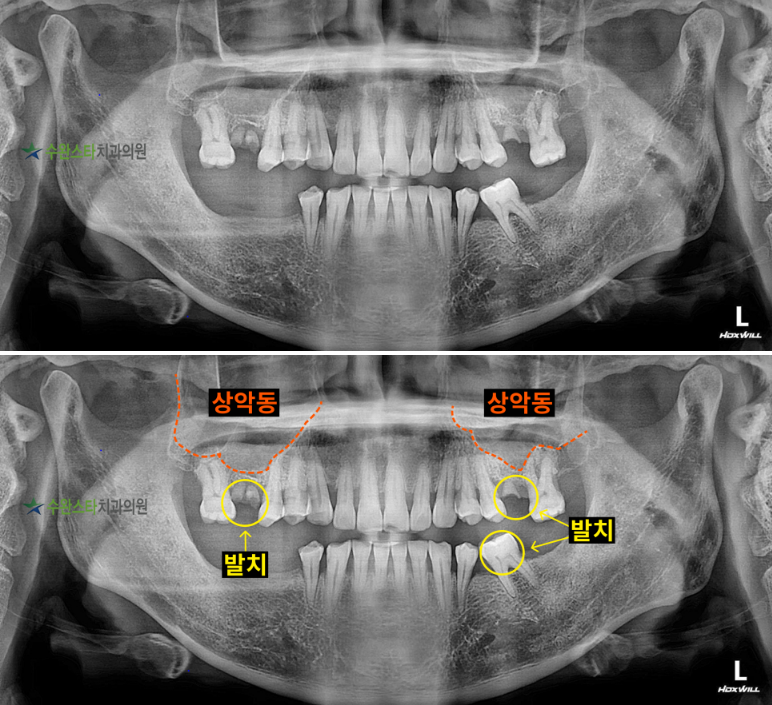

내원 시 파노라마

내원 시 파노라마, 50대 남성 (2025.4 촬영)

내원 시 파노라마 사진입니다.

위아래 잇몸뼈가

심하게 퇴축되어 있는 모습을

볼 수 있으며

특히 어금니의 경우

상실 및 손상된 상태를

오랜 시간 방치하여

잇몸뼈가 많이 녹아있는 상태였고

전체적인 교합도 틀어져 있어

발치 후 뼈 이식을 동반한

임플란트가 필요한데요.